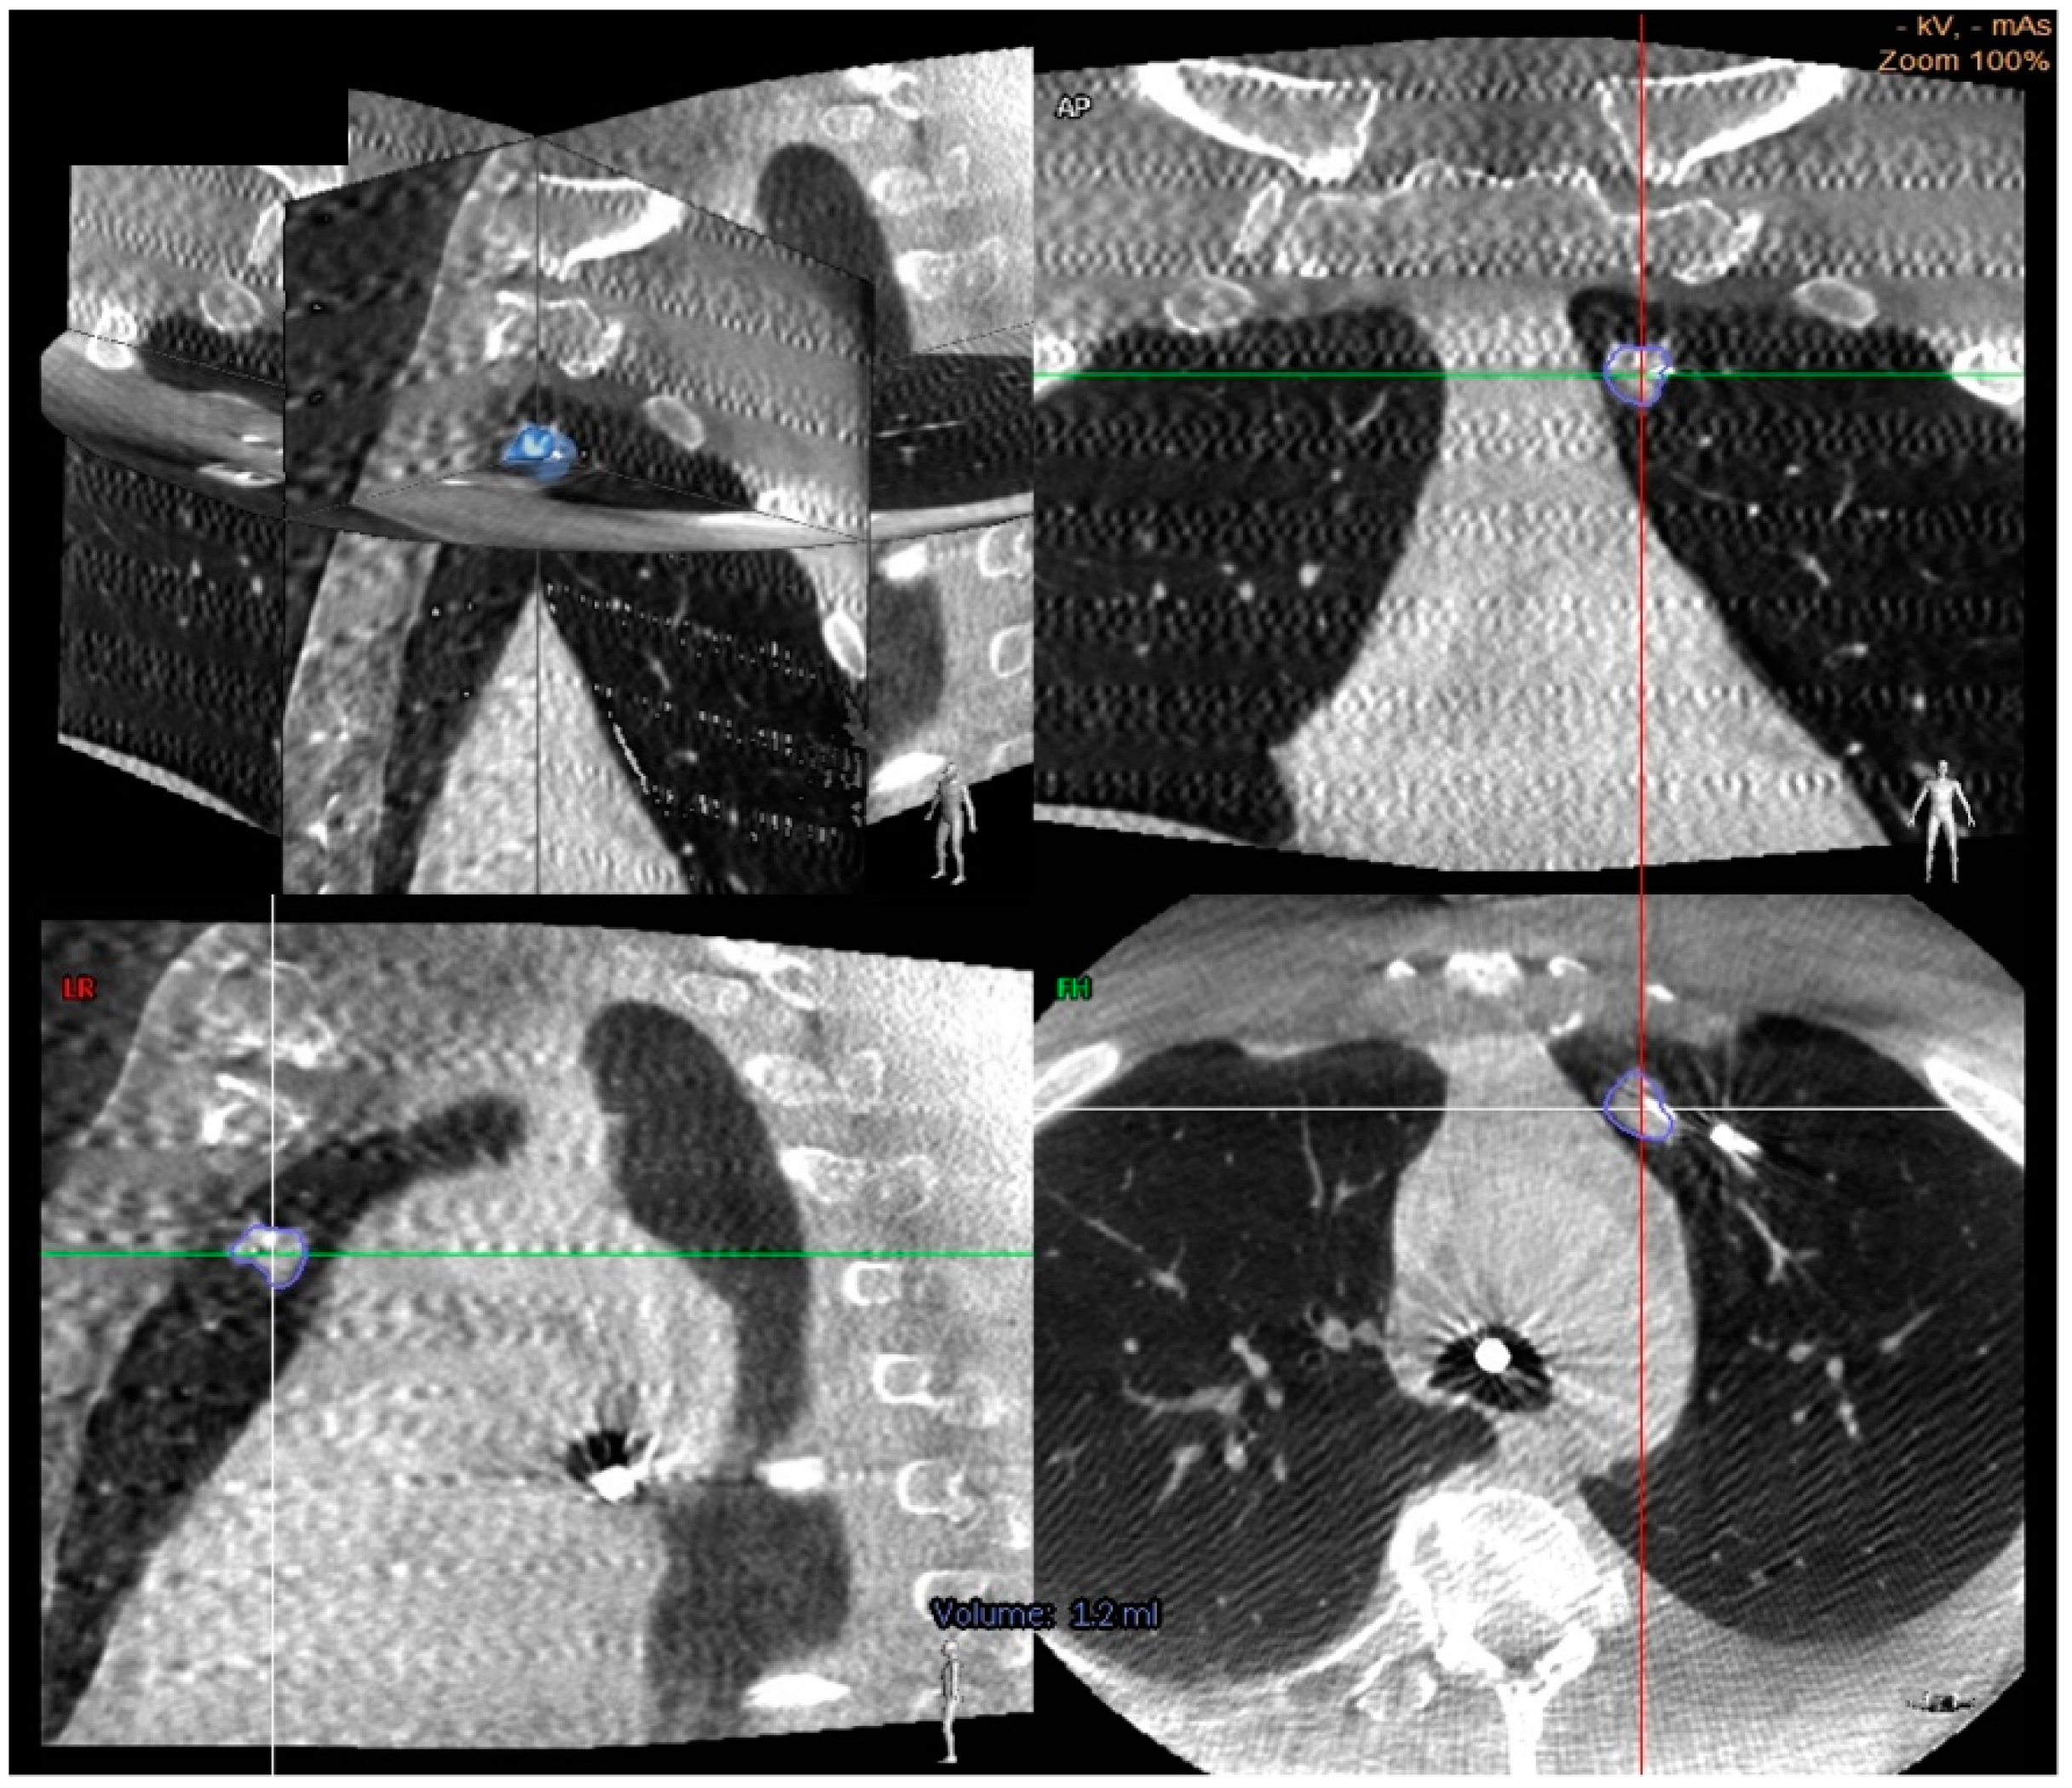

One significant advantage to CBCT is that it reduces the risk of CT-to-body divergence since the CT scan is carried out intra-procedurally. As the many contributors to nodule motion occur during the procedure (respiro-phasic changes, atelectasis, and regional collapse of target lobe due to “over-wedging”), the operator can reimage, adjust if necessary, and resample the targeted area [40]. Additionally, CBCT offers a bypass to instrument deflection by allowing for real-time acquisition of tool in lesion images (Figure 2).

While CBCT allows for excellent real-time imaging capture, the use of guided (augmented) fluoroscopy may offer a higher diagnostic yield and safety profile. Essentially, the patients undergo CBCT imaging, and 3-dimensional segmentation of the nodule is performed using proprietary software. Then, during ENB, the lesion is projected as an overlay on live 2D fluoroscopy, allowing for real-time image guidance. In the largest retrospective study to date involving CBCT guided bronchoscopic biopsy by Pritchett et al. of 93 lesions, the overall DY was 83% using this technique. There was no independent correlation between DY and lesion size, location, visibility under standard fluoroscopy and presence of bronchus sign. The pneumothorax rate was 4% [53]. This study affirmed that augmented fluoroscopy with CBCT imaging is safe and allows for high DY during ENB guided biopsy.

Figure 2. Cone beam CT images demonstrating a center strike represented by a needle within the nodule in axial, coronal, and sagittal planes [56].